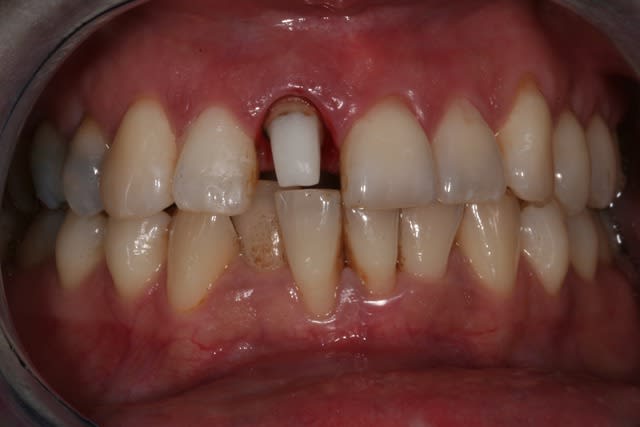

Dès que je peux, je réalise endo + prov + empr dans la séance, et si le cas s'y prête je réalise une RCR collée en profitant du fait que j'ai déjà isolé le champ opératoire:

Gain de temps, diminution du risque de contamination de l'endo pendant les interséances.

Je fais cela depuis déjà 6/7 ans et je m'en porte très bien.

Pour moi deux raisons:

- sourire gingival avec prévision d'une CCC donc je préfère éviter le métal y compris pour la RCR

- racine courte avec perte de substance importante au niveau du logement canalaire (parois résiduelles fines). Dans ces cas là, j'ai peur de la rigidité de l'inlay core, je suis plus à l'aise (intellectuellement parlant, mais j'ai peut être tort) avec un restauration composite collée renforcée par un tenon fibré.